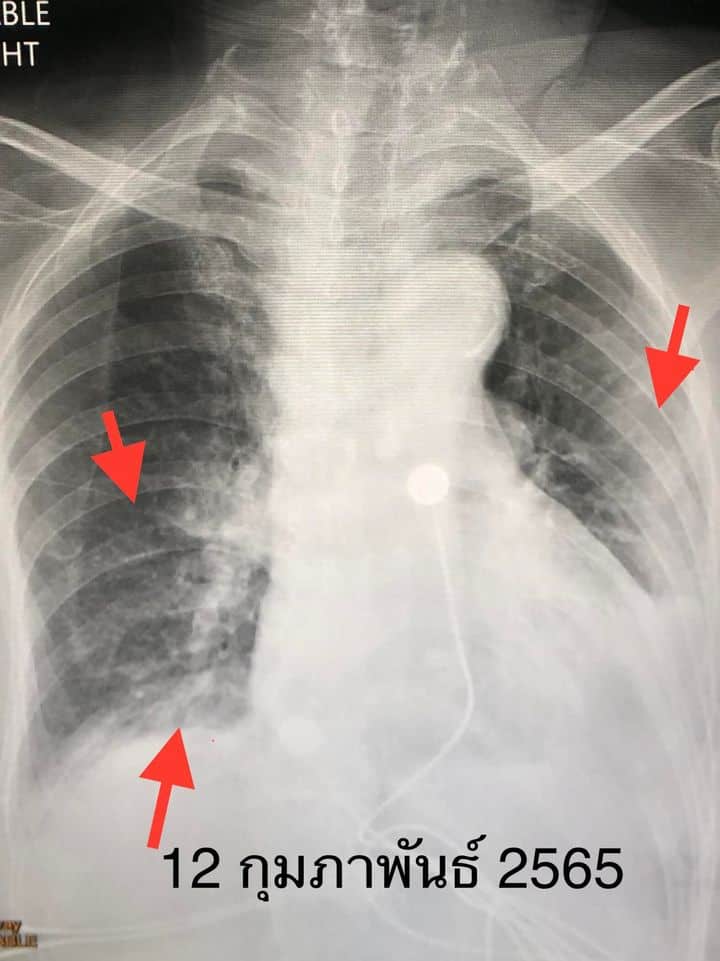

หมอมนูญเตือนต้องฉีดวัคซีนเข็มกระตุ้น หรือวัคซีนเข็ม 3 ลดเสี่ยงเชื้อลงปอด อาการรุนแรง และเสียชีวิต

Ittipan Buathong

นพ.มนูญ ลีเชวงวงศ์ แ ...